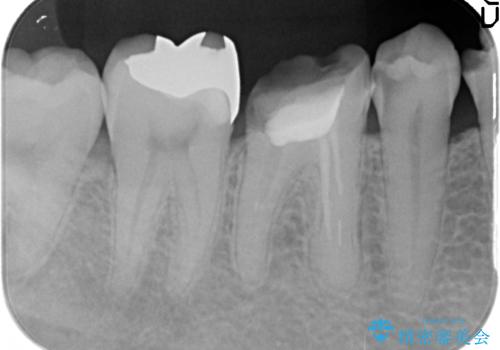

奥歯は神経の治療からやり直し、セラミッククラウンとしました。

大臼歯の再根管治療は横浜桜木町歯科院長 大元先生が担当しました。

- 40万円 内訳:右下6(再根管治療13万円、ジルコニアクラウン10万円、ファイバーコア2万円、仮歯1万円)、右下45(セラミックインレー7万円x2本)費用は治療当時の料金となります

右下6番は、歯肉縁下カリエスではなかったため、そのまま補綴することが可能でした。